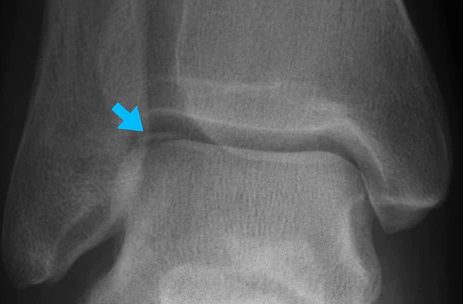

The Talus bone is the highest bone in your ankle and connects to your leg's Tibia and Fibula bones. The Talus bone is vital when it comes to movement and balance. The sites where the top of the Talus bone connects to the Tibia and Fibula bone are referred to as the Talar Dome. The top of the Talus bone is covered in a rubbery substance called cartilage. This protects the bones from scraping together and causing pain. The cartilage also makes sure your ankle joint moves smoothly. Complications arise when the force of a blow damages the bone under...